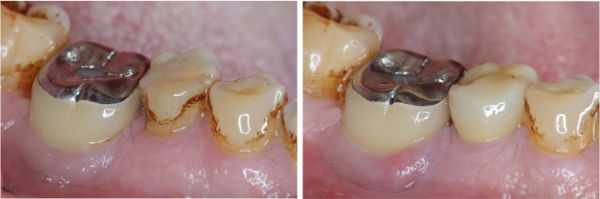

術前、術後比較

幾年下來,這一類連續的治療,長期的癒後相當穩定,因此對於有心保留牙齒的患者,提供了另一個方法,是植牙之外的另一個重要的治療方式。